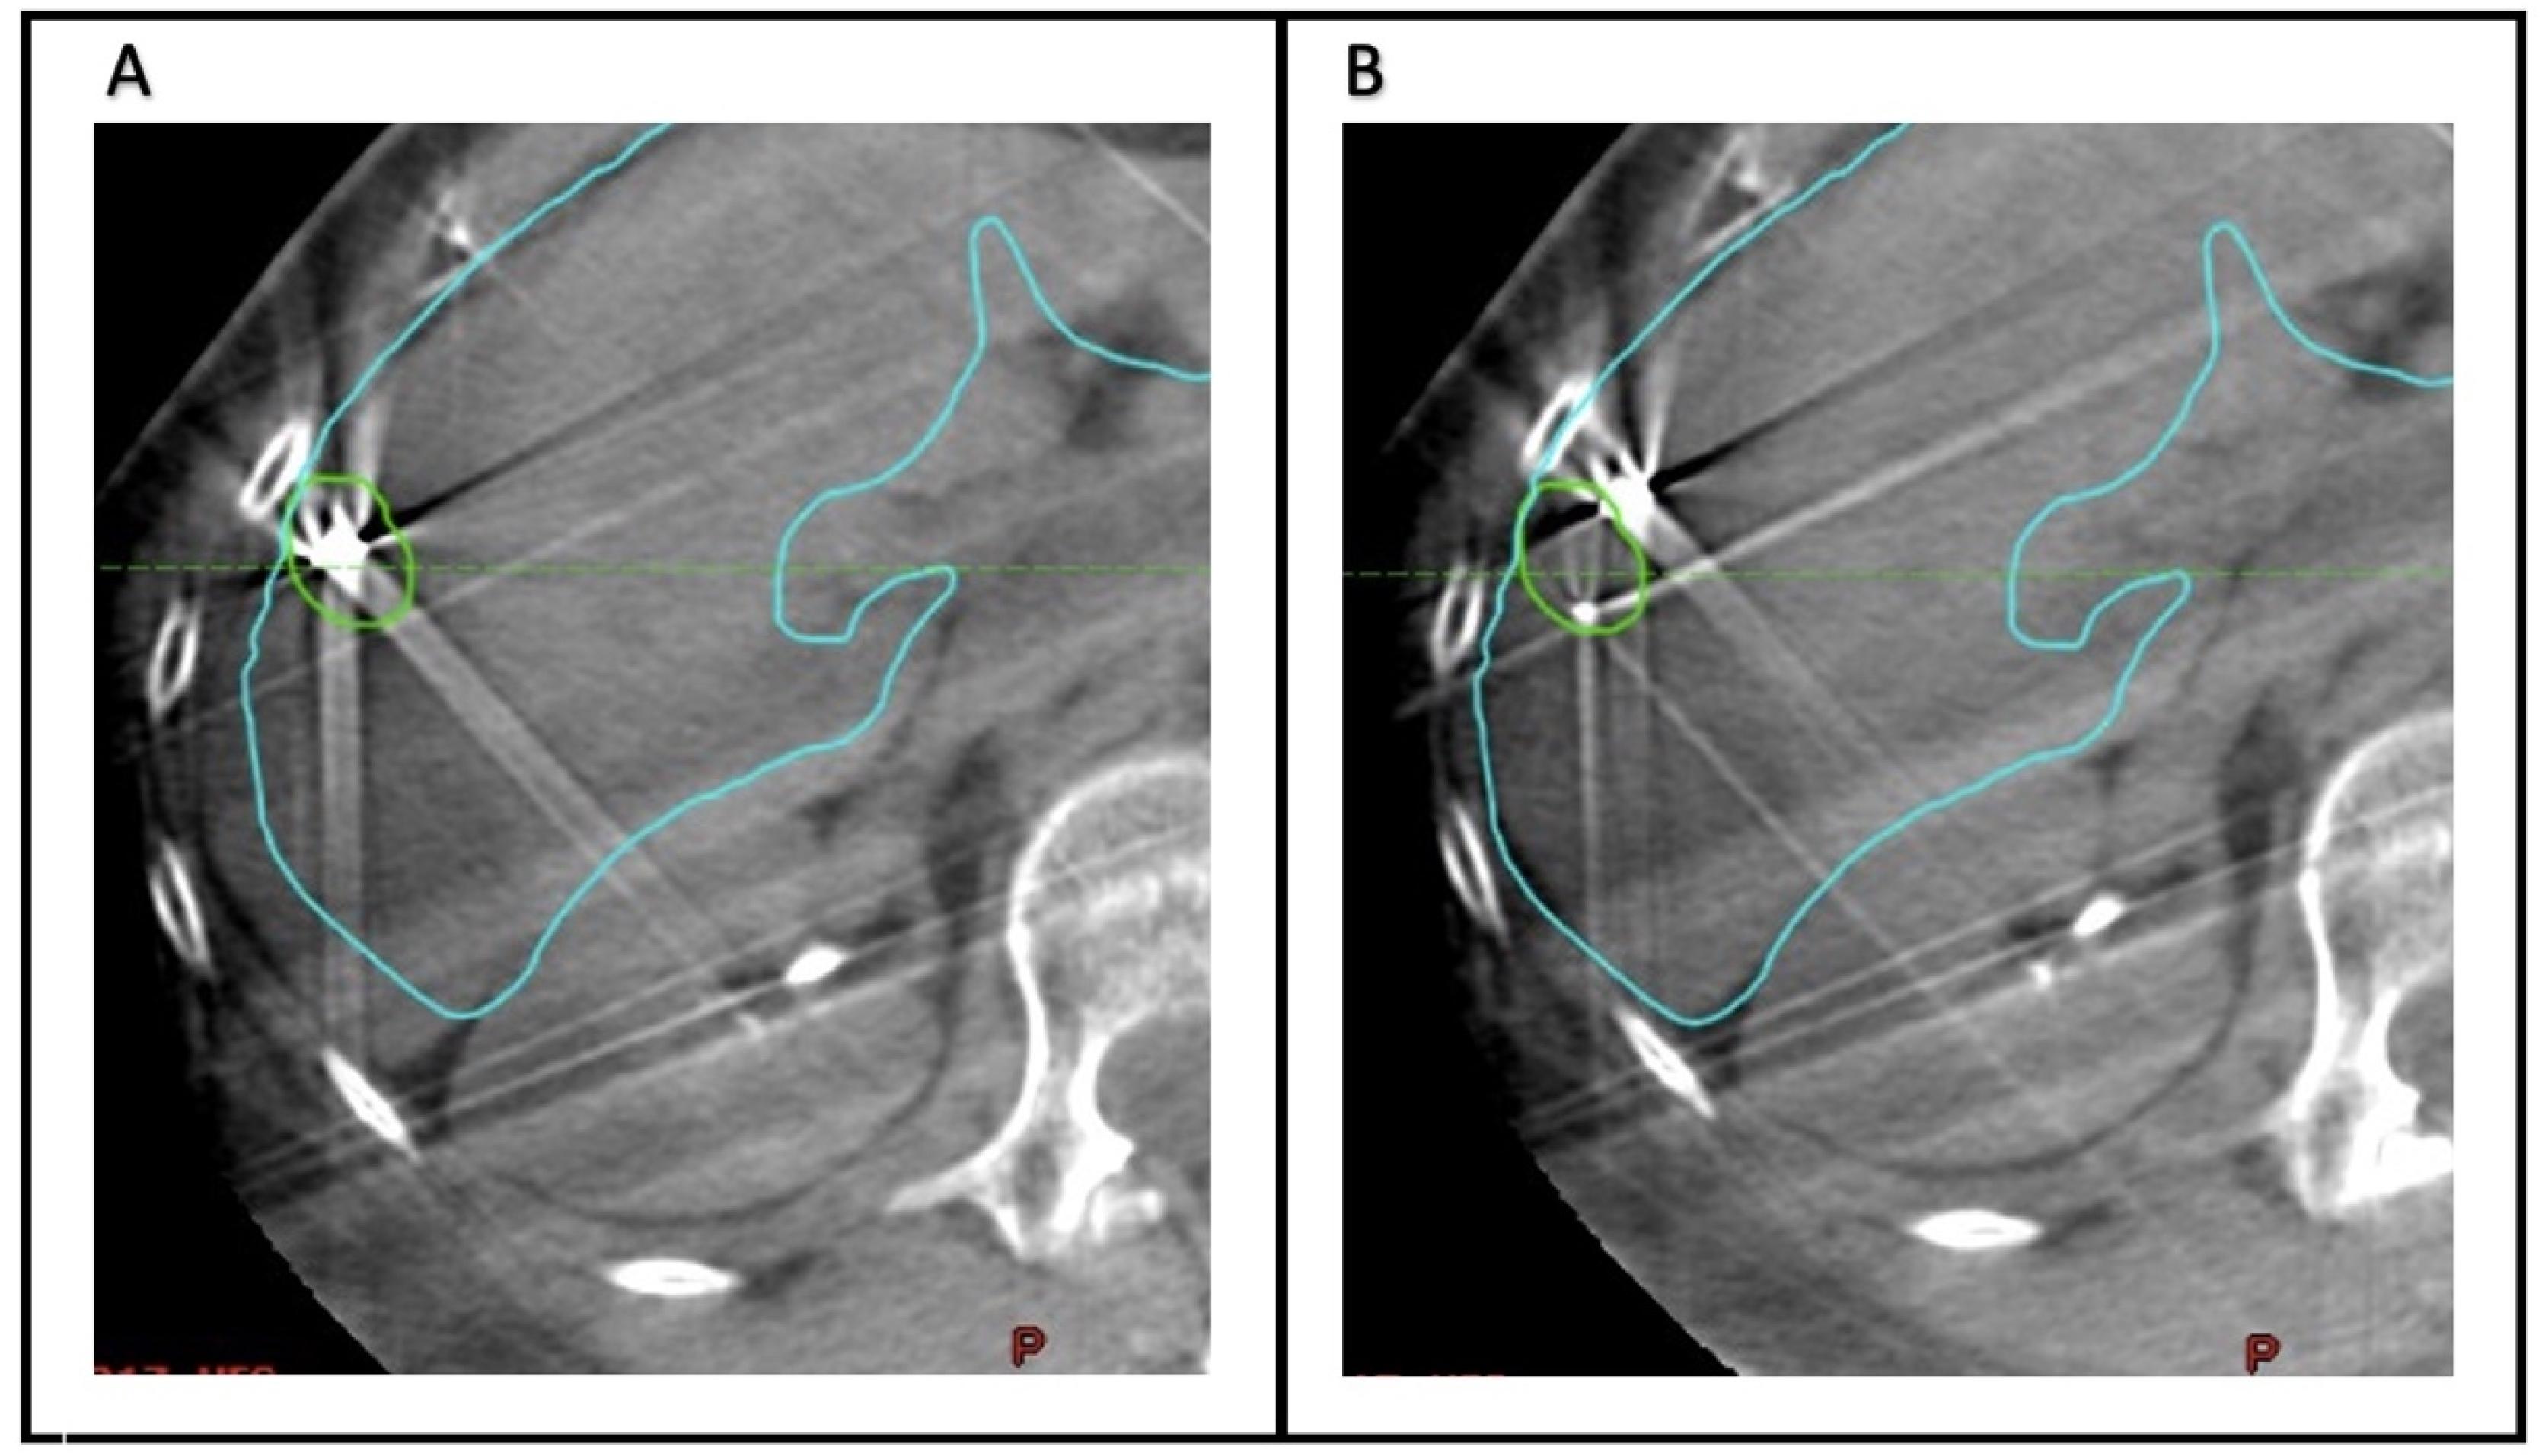

To quantify the accuracy of fiducial marker-based localization, seven observers (Radiation Oncology physicians) retrospectively analyzed the CBCT scans acquired before each fraction. The Aria Eclipse platform was used for target localization through viewing CBCT scans in the offline review mode. For each CBCT, two alignments were performed (

Figure 1). First, the images were aligned to the liver edge in the region of the GTV. Second, the CBCT scan was aligned to the fiducial markers, using the GTV and fiducial marker contours as a guide.

Figure 2 demonstrates examples of concordance between alignment to the liver edge or fiducial markers. In each case, the alignment was reset- to the acquisition position prior to matching. For each alignment, the anterior–posterior (AP), superior–inferior (SI), and lateral or left–right (LR) position was recorded. The mean position across all observers of the CBCT alignments based on fiducial markers was considered the ground truth for subsequent analysis.